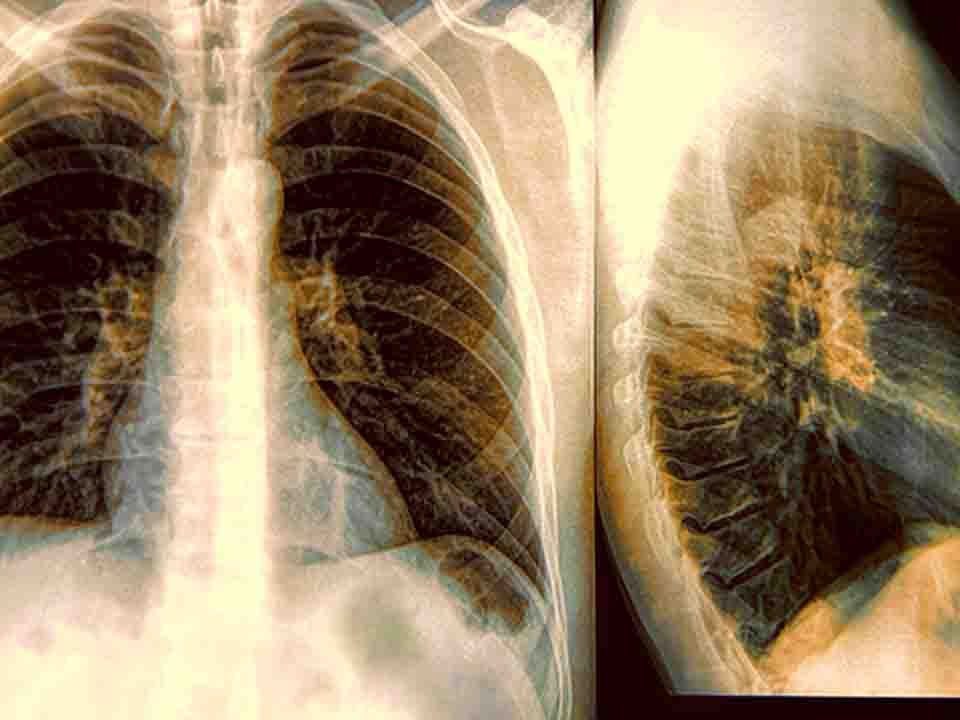

前列腺结核是整个泌尿生殖系统结核病变的一部分,而泌尿生殖系统结核是全身结核的一部分。泌尿生殖系统结核中最多见的是肾结核,其他器官的病变大都继发于肾结核,包括前列腺结核。肾结核的病变愈严重,并发男性生殖系结核的可能性愈高。作为继发性结核,男性生殖系结核很少发生于一个器官,而是同时发生在前列腺、精囊腺、输精管、附睾和睾丸。因此,前列腺结核不是孤立存在的。由于附睾结核常有临床表现,故易早期被患者或医生发现,而前列腺结核较为隐蔽,较难发现。

肺结核得怎样治疗好呢,大家都不想让自己患上疾病,但是一旦患上了疾病就需要积极的治疗,相信朋友们都知道肺结核,而且对于这种疾病也是非常畏惧的,在前些年肺结核可以说是一种不治之症,但是当前的现在,医学的发达,有很多的办法可以治疗此病,接下来为大家介绍一下治疗肺结核的措施,让我们来了解一下吧。

很多的肺结核患者因为此病的发生吗,让他们的生活不再美好,甚至此病如果严重的话,是会夺去人生命的,肺结核不但属于肺部疾病之一,更是一种呼吸道感染疾病,患上之后一定要积极的进行治疗,那么肺结核如何根治呢。